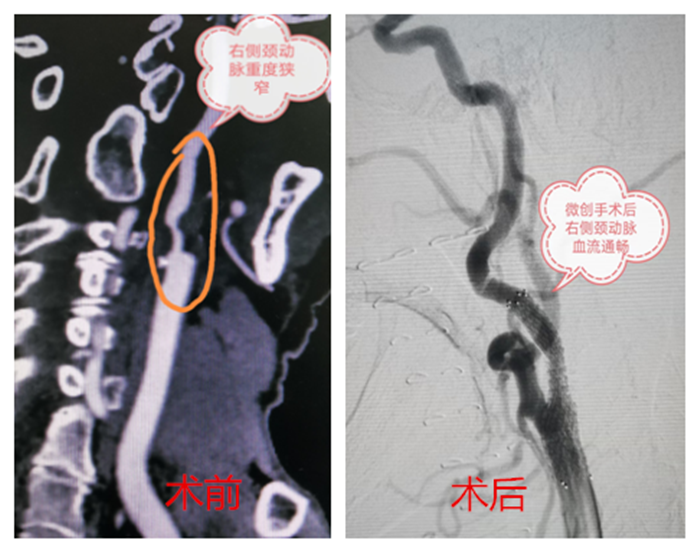

血管外科接診醫(yī)生程國兵仔細問詢并完善相關檢查,經頸動脈CT血管成像提示:右頸內動脈起始段少量混合斑,管腔中重度狹窄。頭顱磁共振提示:右側急性腦梗。

在科主任陸煒的帶領下,血管外科診療團隊為祝老先生行“超選擇性右頸動脈造影+支架植入球囊擴張術”。在非插管全麻下,穿刺右股動脈,置入動脈鞘,導絲通過動脈鞘進入右頸總動脈,在右頸動脈狹窄段遠3厘米處放置保護傘導絲,沿著導絲放置球囊,用球囊壓力泵擴張狹窄段,退出球囊后,在狹窄段成功置入支架。短短一個小時,手術順利完成。